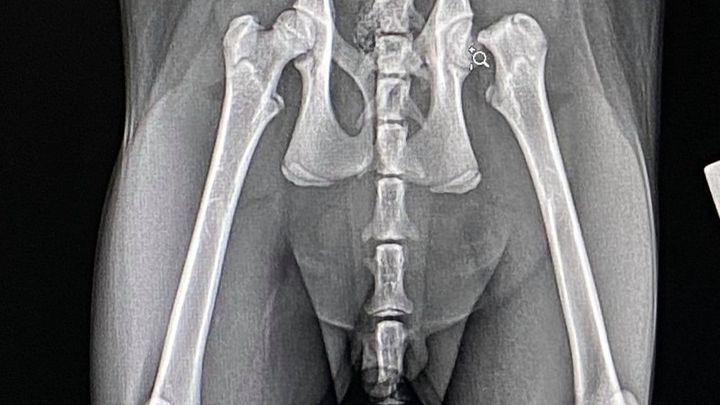

HELP! Dr. Rockey and I had an unfortunate case at the clinic today where the owner has been struggling during this tough year. Her cat jumped from a height and decided to fracture off his femoral head. He needs a much needed FHO and we want to help as much as we can. It's not something we typically do to help raise funds for an owner but this cat in particular belongs to a little girl. So, of course, our hearts melted. Please help us raise money to allow us to save this little girl's kitten.